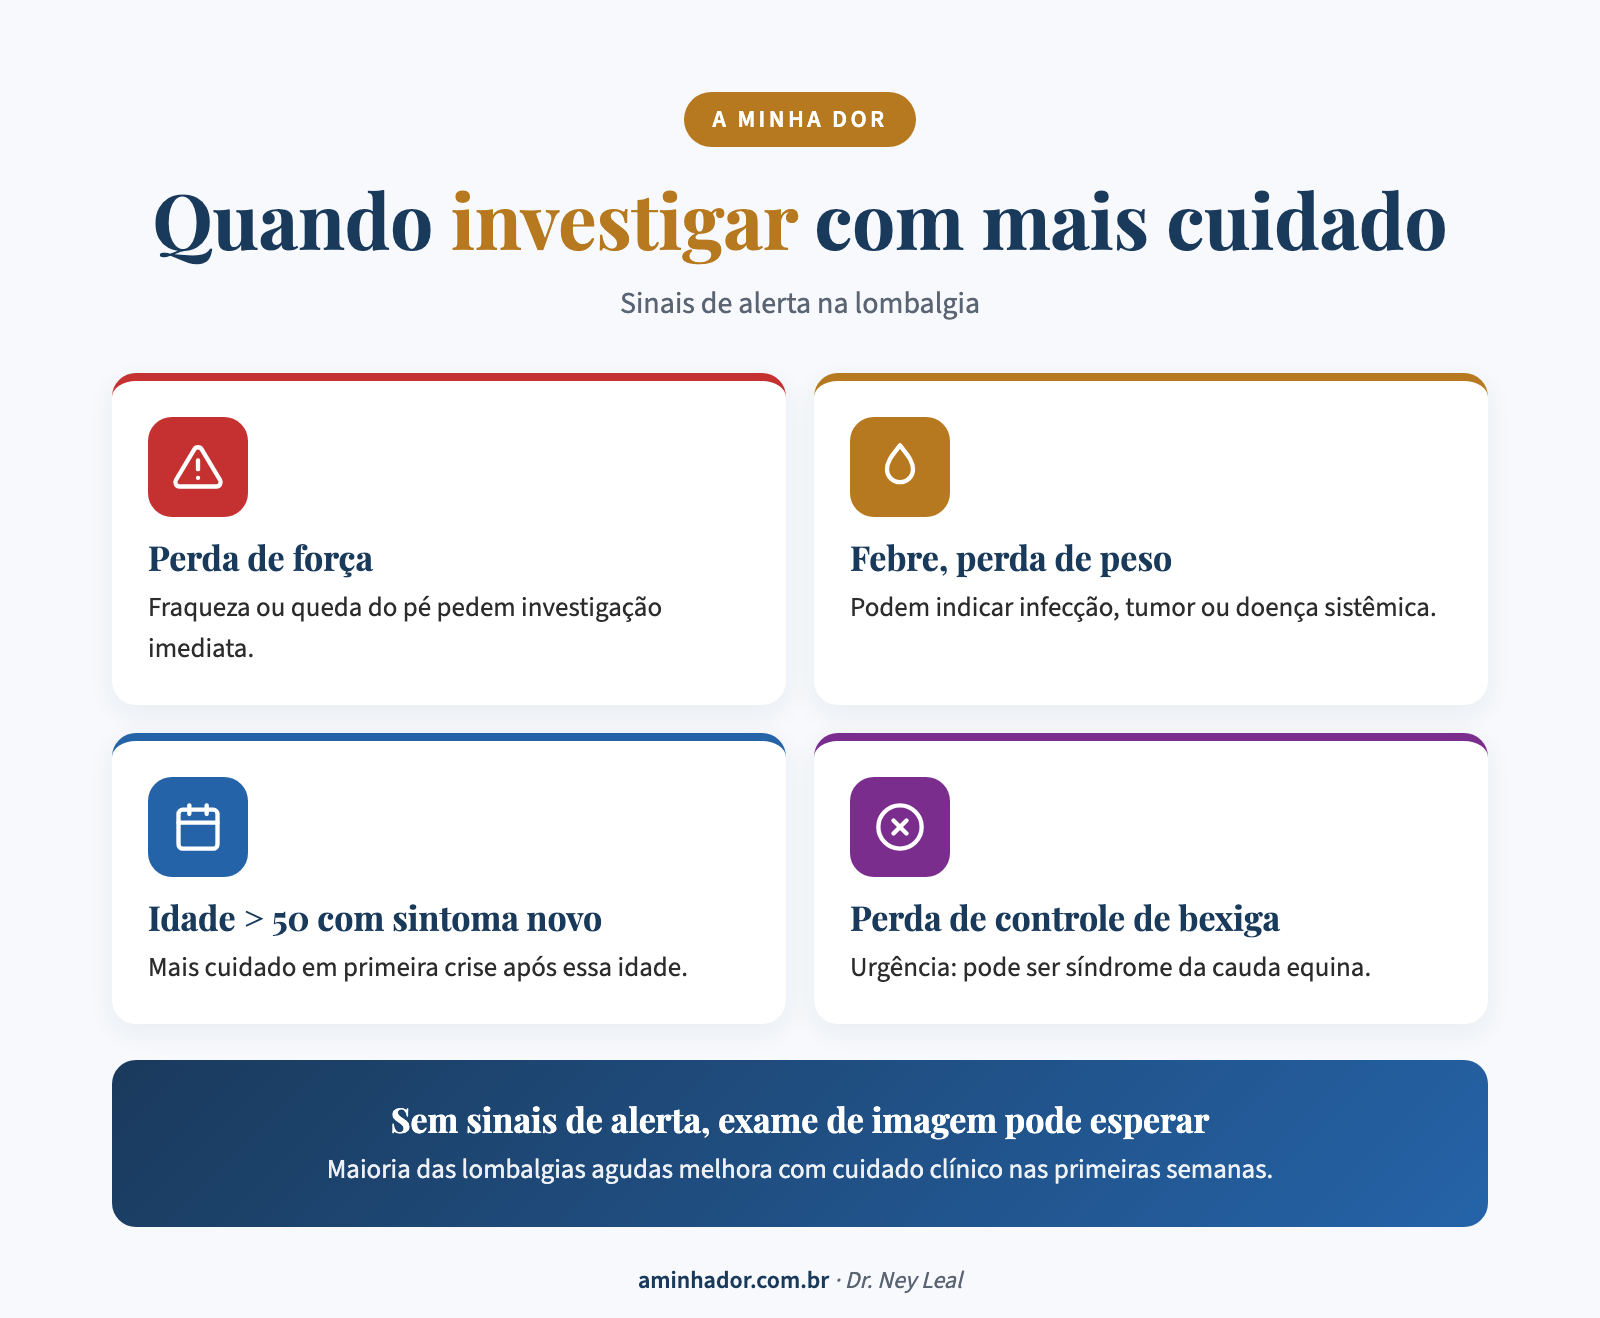

Sinais de alerta: quando a lombalgia precisa de urgência

A maioria dos episódios de lombalgia é benigna. Mas existem sinais que exigem avaliação imediata:

- Perda de controle da bexiga ou intestino

- Fraqueza progressiva nas pernas

- Dormência na região genital

- Dor após trauma (queda, acidente)

- Febre associada à dor lombar

- Perda de peso inexplicada

- Dor que piora à noite e não alivia com repouso

Se você tem algum desses sintomas, procure atendimento médico imediato.

Diagnóstico: por que o exame não conta a história toda

Na maioria dos casos, o diagnóstico da lombalgia é clínico, feito pela conversa e pelo exame físico. Exames de imagem (ressonância, raio-X) são indicados quando há sinais de alerta, quando a dor não melhora depois de 4 a 6 semanas de tratamento, ou quando há suspeita de outra causa específica.

Quando devo procurar um médico para dor lombar?

Procure atendimento médico se a dor durar mais de 4 semanas sem melhora, se estiver piorando, se irradiar para a perna, ou se houver sinais de alerta como perda de força nas pernas, alteração no controle da bexiga ou intestino, febre ou perda de peso inexplicada. Nesses casos, a avaliação deve ser imediata.